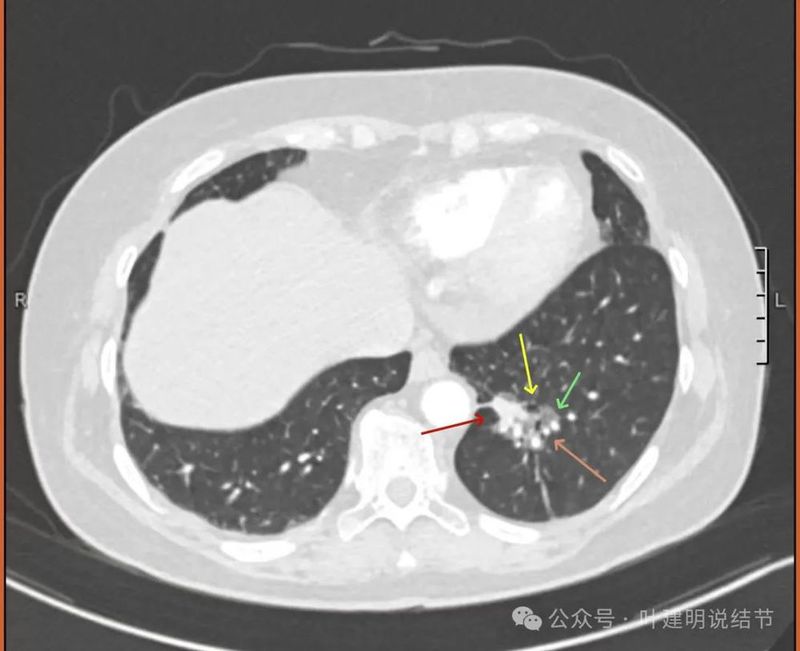

外院增强CT影像:

左下病灶混合密度,实性成分明显,但收缩力不强,磨玻璃成分非常明显,而且轮廓与边界清楚,灶内有小空泡征,表面有分叶,灶内有多支血管走行。

纵隔窗见有明显实性成分,磨玻璃成分不可见,走行血管也明显。

纵隔与肺门没有见到显著增大融合要考虑转移的淋巴结。